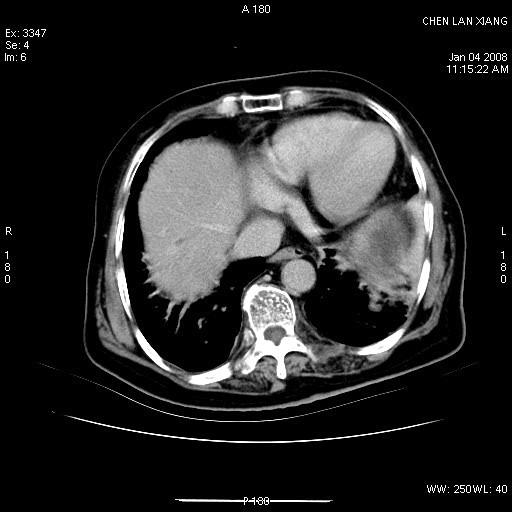

标题: CT11180:女,76岁,腹痛3-4天 [打印本页]

女,76岁,腹痛3-4天,b超示:肝内实性肿物,胆囊强回声,胆总管扩张.

考虑:1、胆总管下端结石伴梗阻性肝内外胆管扩张(肝左叶外侧段肝内胆管多发结石、胆管炎);

2、肿囊癌累及肝,不除外 黄色肉芽肿性胆囊炎。

1 胆总管末端结石伴肝内胆管结石,肝内外胆管扩张。2 胆囊扩大,胆囊壁不规则增厚,内见软组织密度影。考虑:慢性胆囊炎,不除外胆囊癌!

胆总管末端结石伴肝内胆管结石,肝内外胆管扩张。低位胆道梗阻2 胆囊扩大,胆囊壁不规则增厚,内见软组织密度影。考虑:慢性胆囊炎,不除外胆囊癌!

胆囊内结增强影,肝内胆管、胆总管扩张明显。肝内胆管、胆总管下段多发结石,胆囊癌,建议mrcp检查

肝内外胆管多发结石;胆囊癌;

胆囊密度增高,增强后周边肝组织及胆囊窝下部周边软组织延时性不规则强化.然胆囊壁未见明显不规则增厚及肿块.左侧肝内胆管及胆总管下段结石伴胆系扩张.

考虑;胆囊炎(黄色肉芽肿性胆囊炎?),左侧肝内胆管及胆总管下段结石.

ct所见:1、 肝内胆管结石,肝内外胆管扩张。低位胆道梗阻,胆总管下端结石;2 胆囊扩大,胆囊壁不规则增厚

考虑:胆总管下端结石并肝内外胆管扩张,肝内胆管结石;

慢性胆囊炎

标题: 肝右叶病灶

胆囊癌侵犯肝右叶?

1)胆囊癌伴肝脏转移。2)胆总管下端结石、肝内胆管结石伴肝内外胆管扩张。